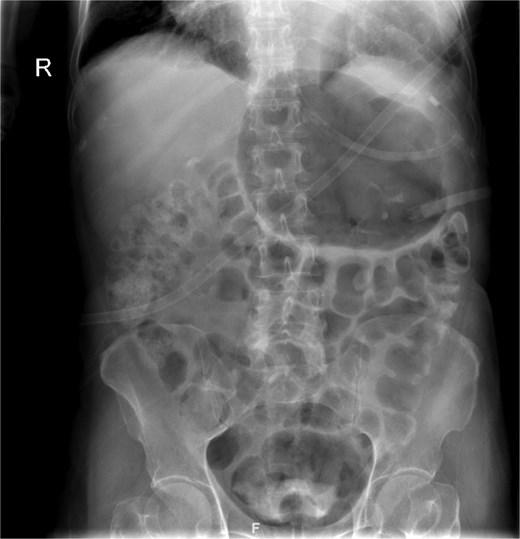

The patient was admitted under the care of the general surgery department, and he was taken to the operating room for a laparoscopic exploration, which showed mesenteroaxial gastric volvulus, wandering spleen, and a large hiatal hernia which was ~5 cm in size. No devitalized tissues were found. An attempt at intraoperative endoscopy failed to pass through the hiatus. A cruroplasty with a Toupet fundoplication and gastropexy were done as shown in (Figs 3 and 4). On the third postoperative day, the patient was doing well. He was tolerating oral intake and passing regular motions and was discharged home in good condition as he was traveling to his country.

(a) Intraoperative image revealing the position of the stomach without any devitalized tissue. (b) A large hiatal hernia after completion of dissection in preparation for cruroplasty with a Toupet fundoplication.